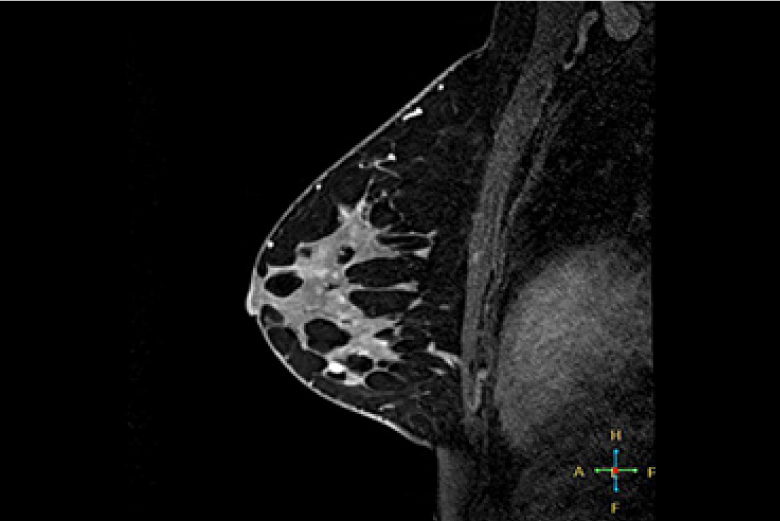

乳腺MRI

MRI(磁気共鳴画像)

MRIとは、Magnetic Resonance Imaging の略で磁気共鳴断層撮影装置と呼ばれ、強い磁場の中で、人体内の水素原子核に電波を与え、そこから発生した電波を受し画像化する検査です。

当院では令和8年1月に1.5 テスラの最先端MRI装置を導入し、従来の3.0テスラMRI装置と2台で検査を行っています。

MRIは、X線撮影(一般撮影・CT)では描出できない脳・脊髄・椎間板・半月板・筋肉・腱・血管などの描出に優れています。また、人体の様々な断面像が得られるのと同時にX線を使わないため被ばくの心配がありません。

急性期の脳梗塞の診断に優れ、脳外科領域において非常に有用な検査です。軟部組織のコントラストに優れ、外科・整形外科・婦人科・泌尿器科の検査に有用です。